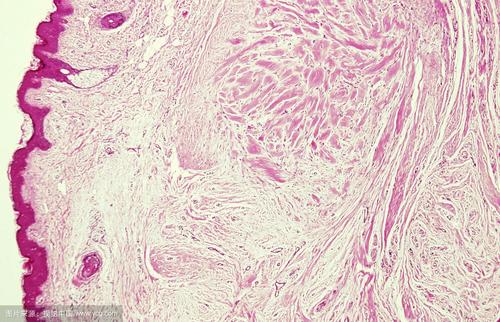

皮肤损伤后修复过程中结缔组织对创伤的反应超过正常范围,形成瘢痕并继续长大。实质上是胶原纤维过度增生及透明性变而形成的一种疾病。

ß射线的电离辐射能产生生物效应,导致病变局部组织细胞出现️①形态改变:如核固缩、核溶解、核碎裂、胞质内空泡形成、线粒体破碎、溶酶体破坏等。

② 功能改变:如细胞活力降低、生长抑制、代谢紊乱、增殖能力降低、分泌功能减低或停止、细胞膜通透性改变及细胞凋亡等。